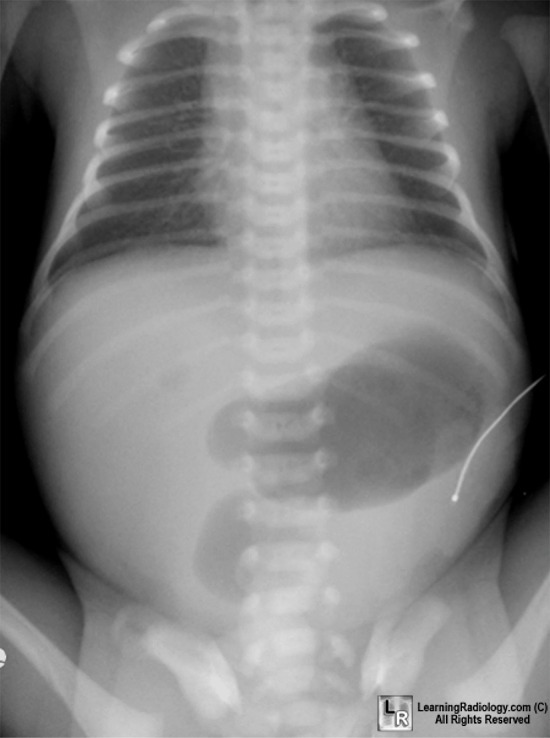

Duodenal atresia:

Failure of recanalization of the Duodenum in early gestation

Double bubble-sing on x-ray; dilated stomach and promximal duodenum

Most common GI abnormality associated with Down Syndrome

vomit contains BILE